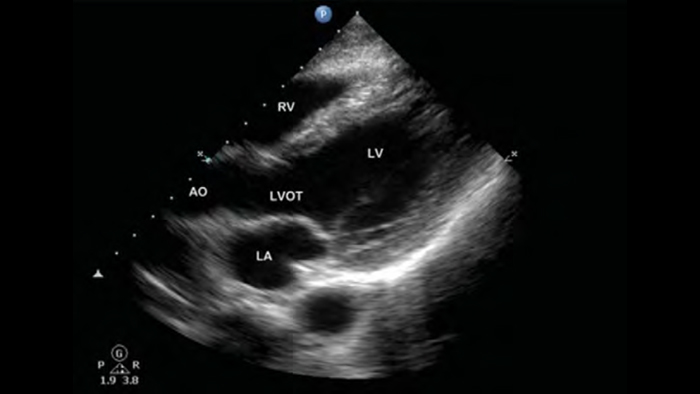

Lumify helpt u de plaatsing van de naalden, de omringende zenuwen, vaten en fascia-vlakken duidelijk te visualiseren.

Beter beeld voor meer vertrouwen

Lumify kan helpen de subtiele details van een beeld zichtbaar te maken en afwijkende weefselstructuren bloot te leggen vanuit verschillende hoeken. Hierdoor kunt u met vertrouwen realtime beslissingen nemen, van diagnose tot herstel.